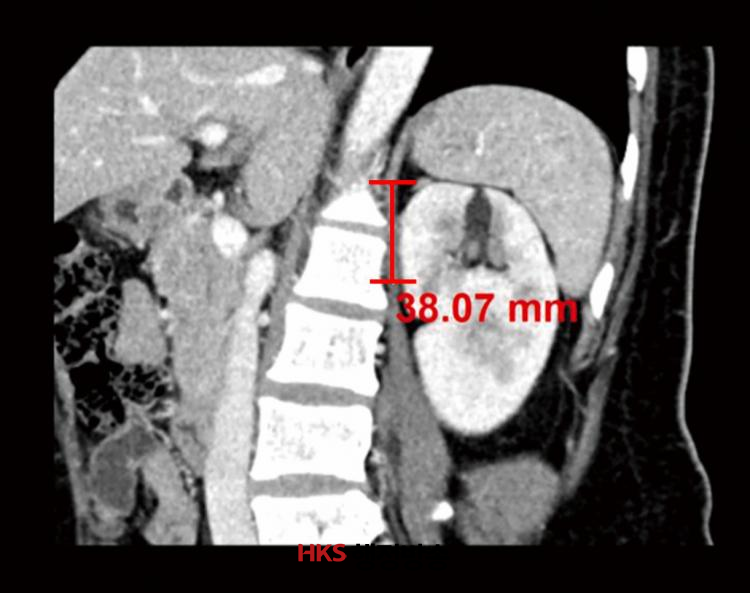

ÀÌ ¿¬±¸¿¡¼ ´Ùº¯·® ·ÎÁö½ºÆ½ ȸ±ÍºÐ¼®*À» ÅëÇØ ¼ö¼ú½Ã°£°ú ȯÀÚµéÀÇ ¡ã¼ºº° ¡ã¿¬·É ¡ã±âÀúÁúȯ ¡ãÁ¾¾çÀÇ Æ¯¼º µîÀ» ºÐ¼®ÇØ ¼ö¼ú½Ã°£ ¿¬Àå ¿¹ÃøÀÎÀÚµéÀ» È®ÀÎÇÑ °á°ú ºÎ½ÅÁ¾¾ç ÇϺο¡¼ ½ÅÀå »óºÎ±îÁöÀÇ ¼öÁ÷ °Å¸®(±×¸²1)°¡ ¼ö¼ú½Ã°£À» ¿¬Àå½ÃŰ´Â ÁÖ¿ä ¿¹ÃøÀÎÀÚÀÎ °ÍÀ¸·Î ¹àÇôÁ³´Ù.

<±×¸²1> ºÎ½ÅÁ¾¾ç ÇϺο¡¼ ½ÅÀå »óºÎ±îÁöÀÇ ¼öÁ÷ °Å¸®